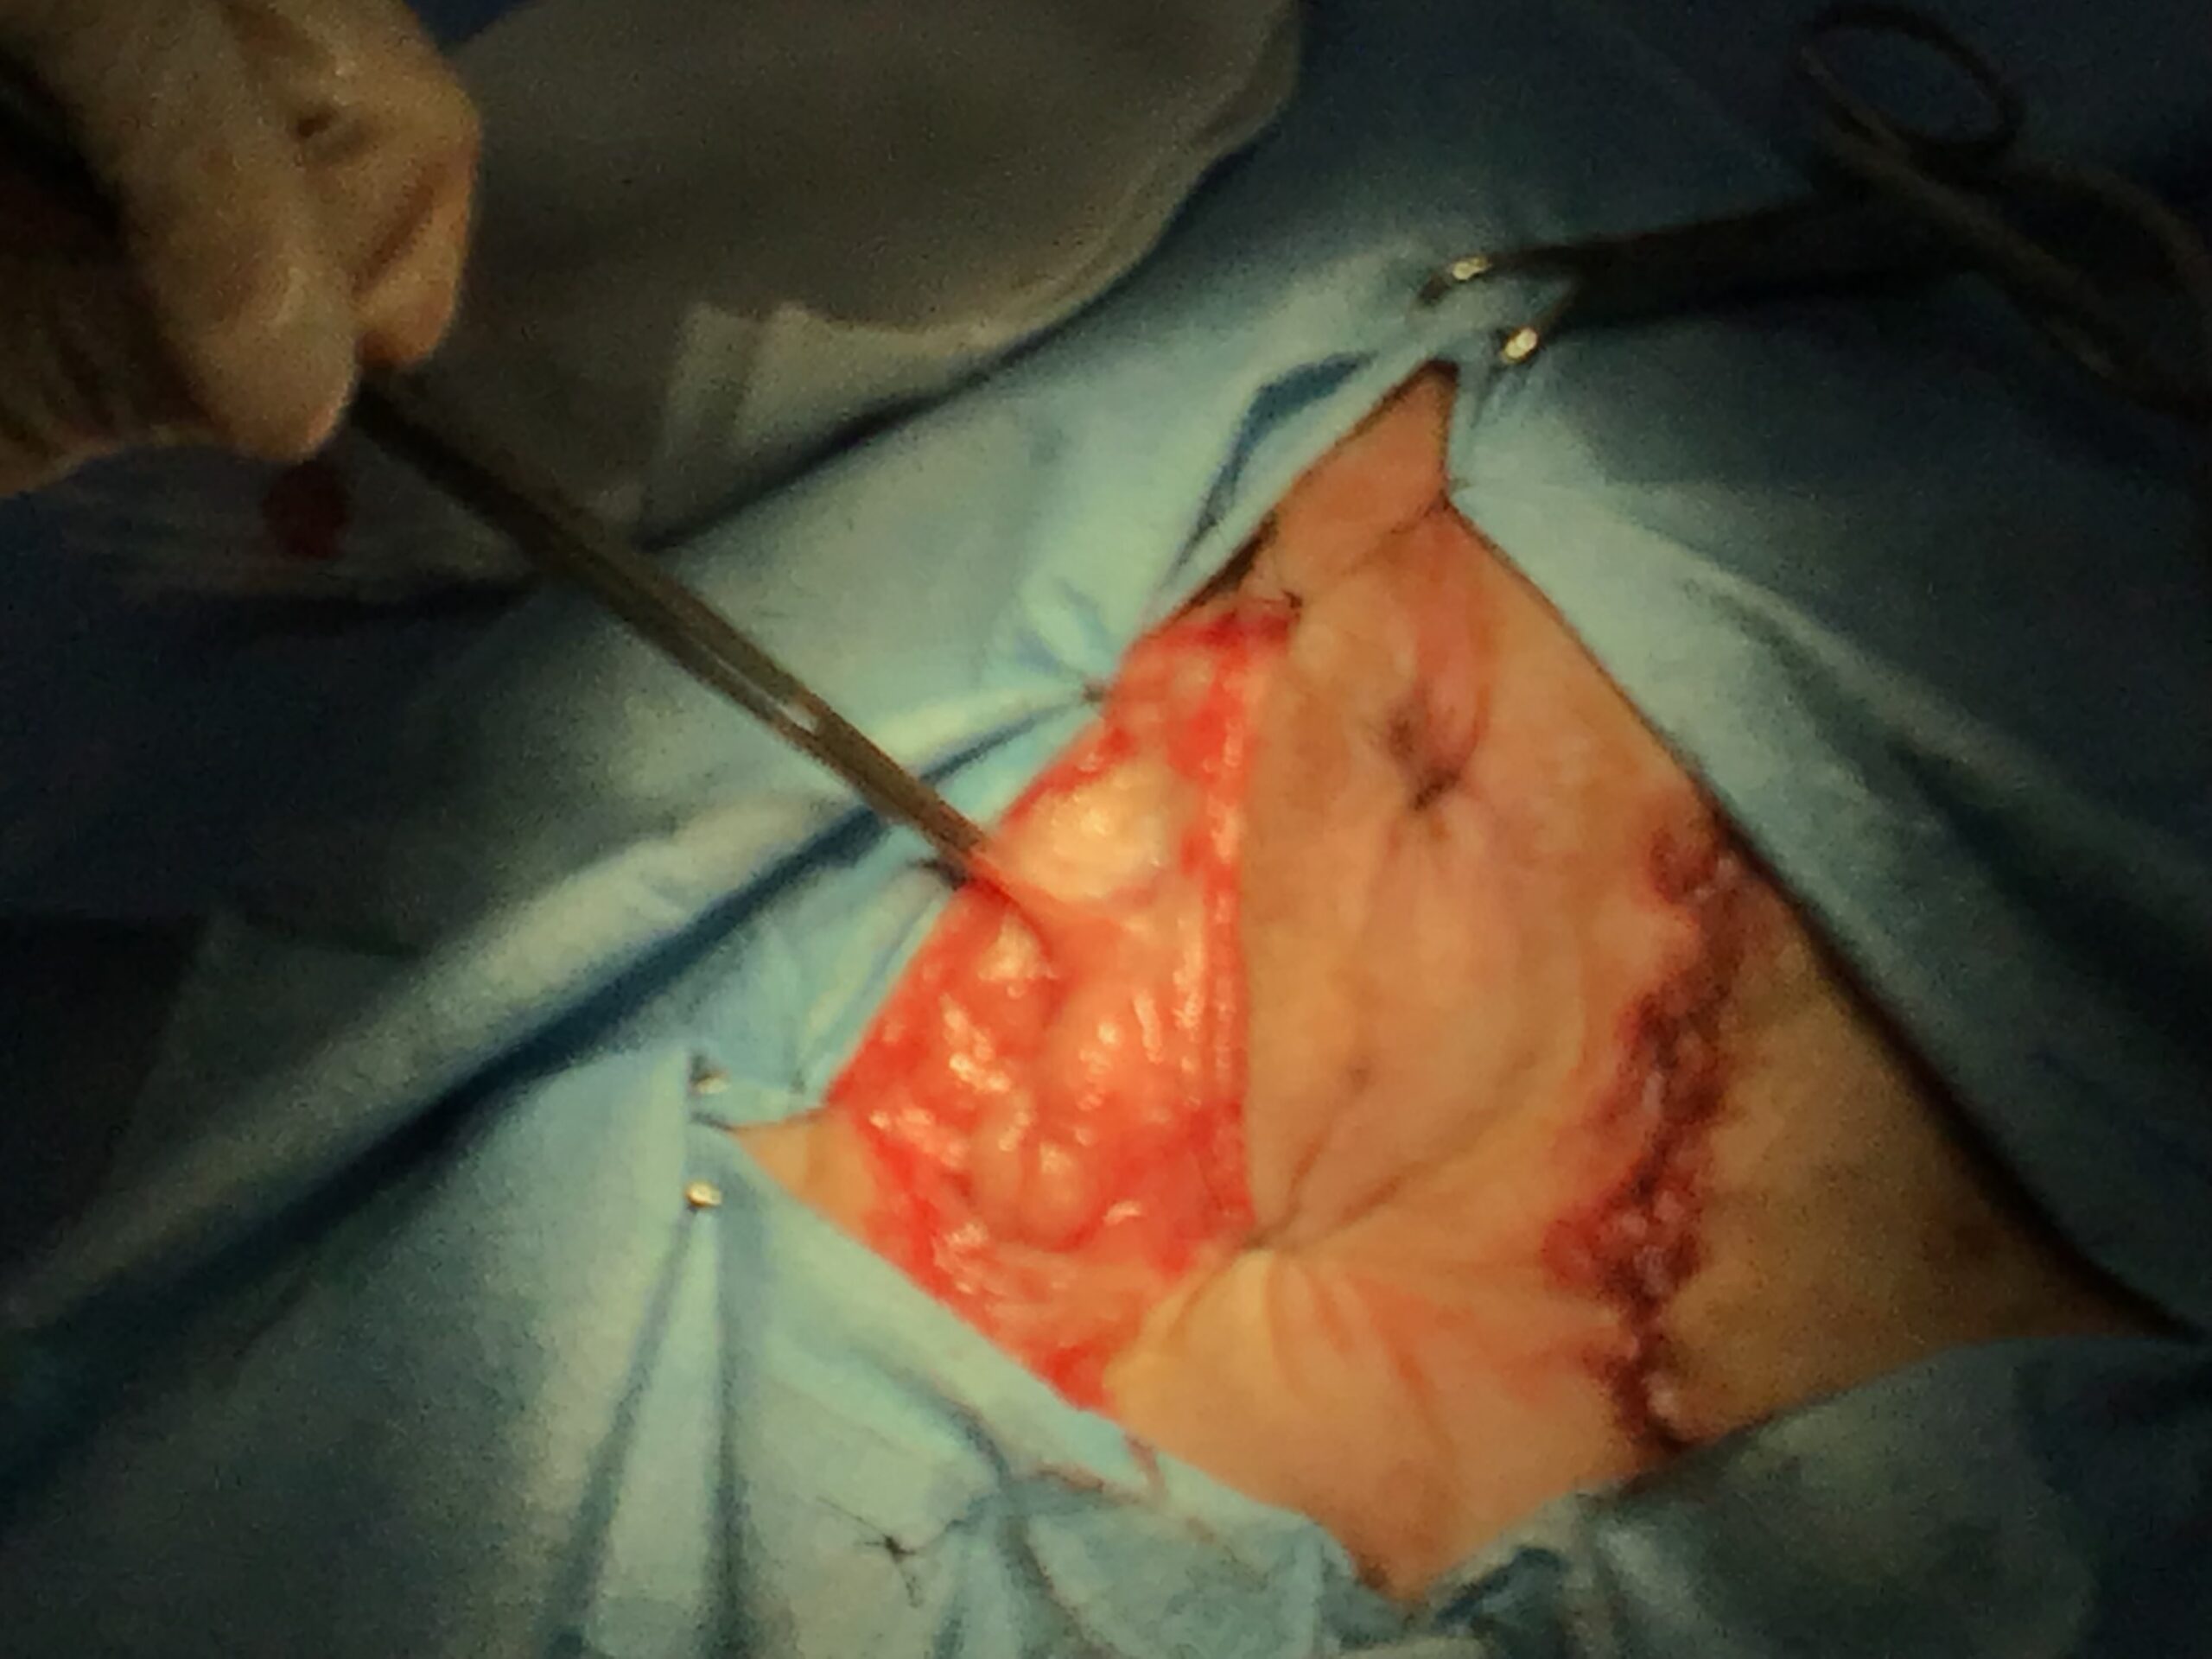

本症例(初診時高齢・小型犬)は、当初、自力での排便が困難となる「会陰ヘルニア」および「直腸憩室(腸の一部がポケット状に広がる状態)」を主訴に来院されました。複数回の手術を経てヘルニアを管理していましたが、のちに激しい嘔吐と食欲不振、極端な肝機能数値の異常(測定不能レベルの上昇)を呈し、超音波検査で肝臓に腫瘤(マス)が発見されました。

本症例には、時期を分けて2つの大きな外科的介入を行いました。

This post details our surgical and medical approach to a complex case involving recurrent severe perineal hernia and a malignant liver lymphoma in a senior dog. We emphasize the grim reality of untreated conditions and the severe risks of anesthesia when underlying heart and respiratory diseases are present. To maximize safety, we exclusively use local infiltration anesthesia. Due to a lack of available autologous tissue, a polypropylene mesh and extensive organ pexy (both colon and bladder fixation to the abdominal wall) were required to prevent fatal urethral obstruction and re-herniation. Additionally, simultaneous castration was performed to shrink the enlarged prostate, a key factor in hernia development, thereby reducing the risk of recurrence. For the liver tumor, given its deep location at the liver base and the high risk of fatal bleeding, we opted for a biopsy which confirmed lymphoma. Unfortunately, the patient’s elevated bilirubin and the family’s preference for a compromised, single-agent chemotherapy protocol led to early drug resistance. We candidly discuss the harsh realities of end-stage cancer—it is a painful decline characterized by severe cachexia and organ failure that palliative care can only partially ease. Furthermore, we outline our strict early discharge policy (1-3 days), the physical limitations of our unstaffed overnight remote monitoring, and our referral policy for highly specialized surgeries. We believe in providing honest, logical medical facts rather than false hope, ensuring families can make fully informed and responsible decisions.